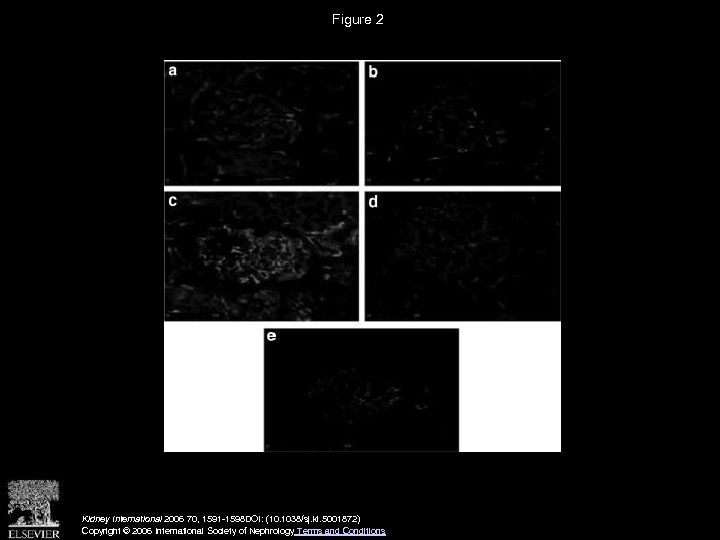

Figure 2 Kidney International 2006 70, 1591 -1598 DOI: (10. 1038/sj. ki. 5001872) Copyright © 2006 International Society of Nephrology Terms and Conditions